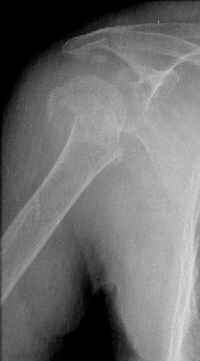

This fx need to be manipulated, reduced and fixed. We developed a minimally invasive ex fix with Ilizarov parts to fix it, we call it “Spider”, which can hold 4 fragments.